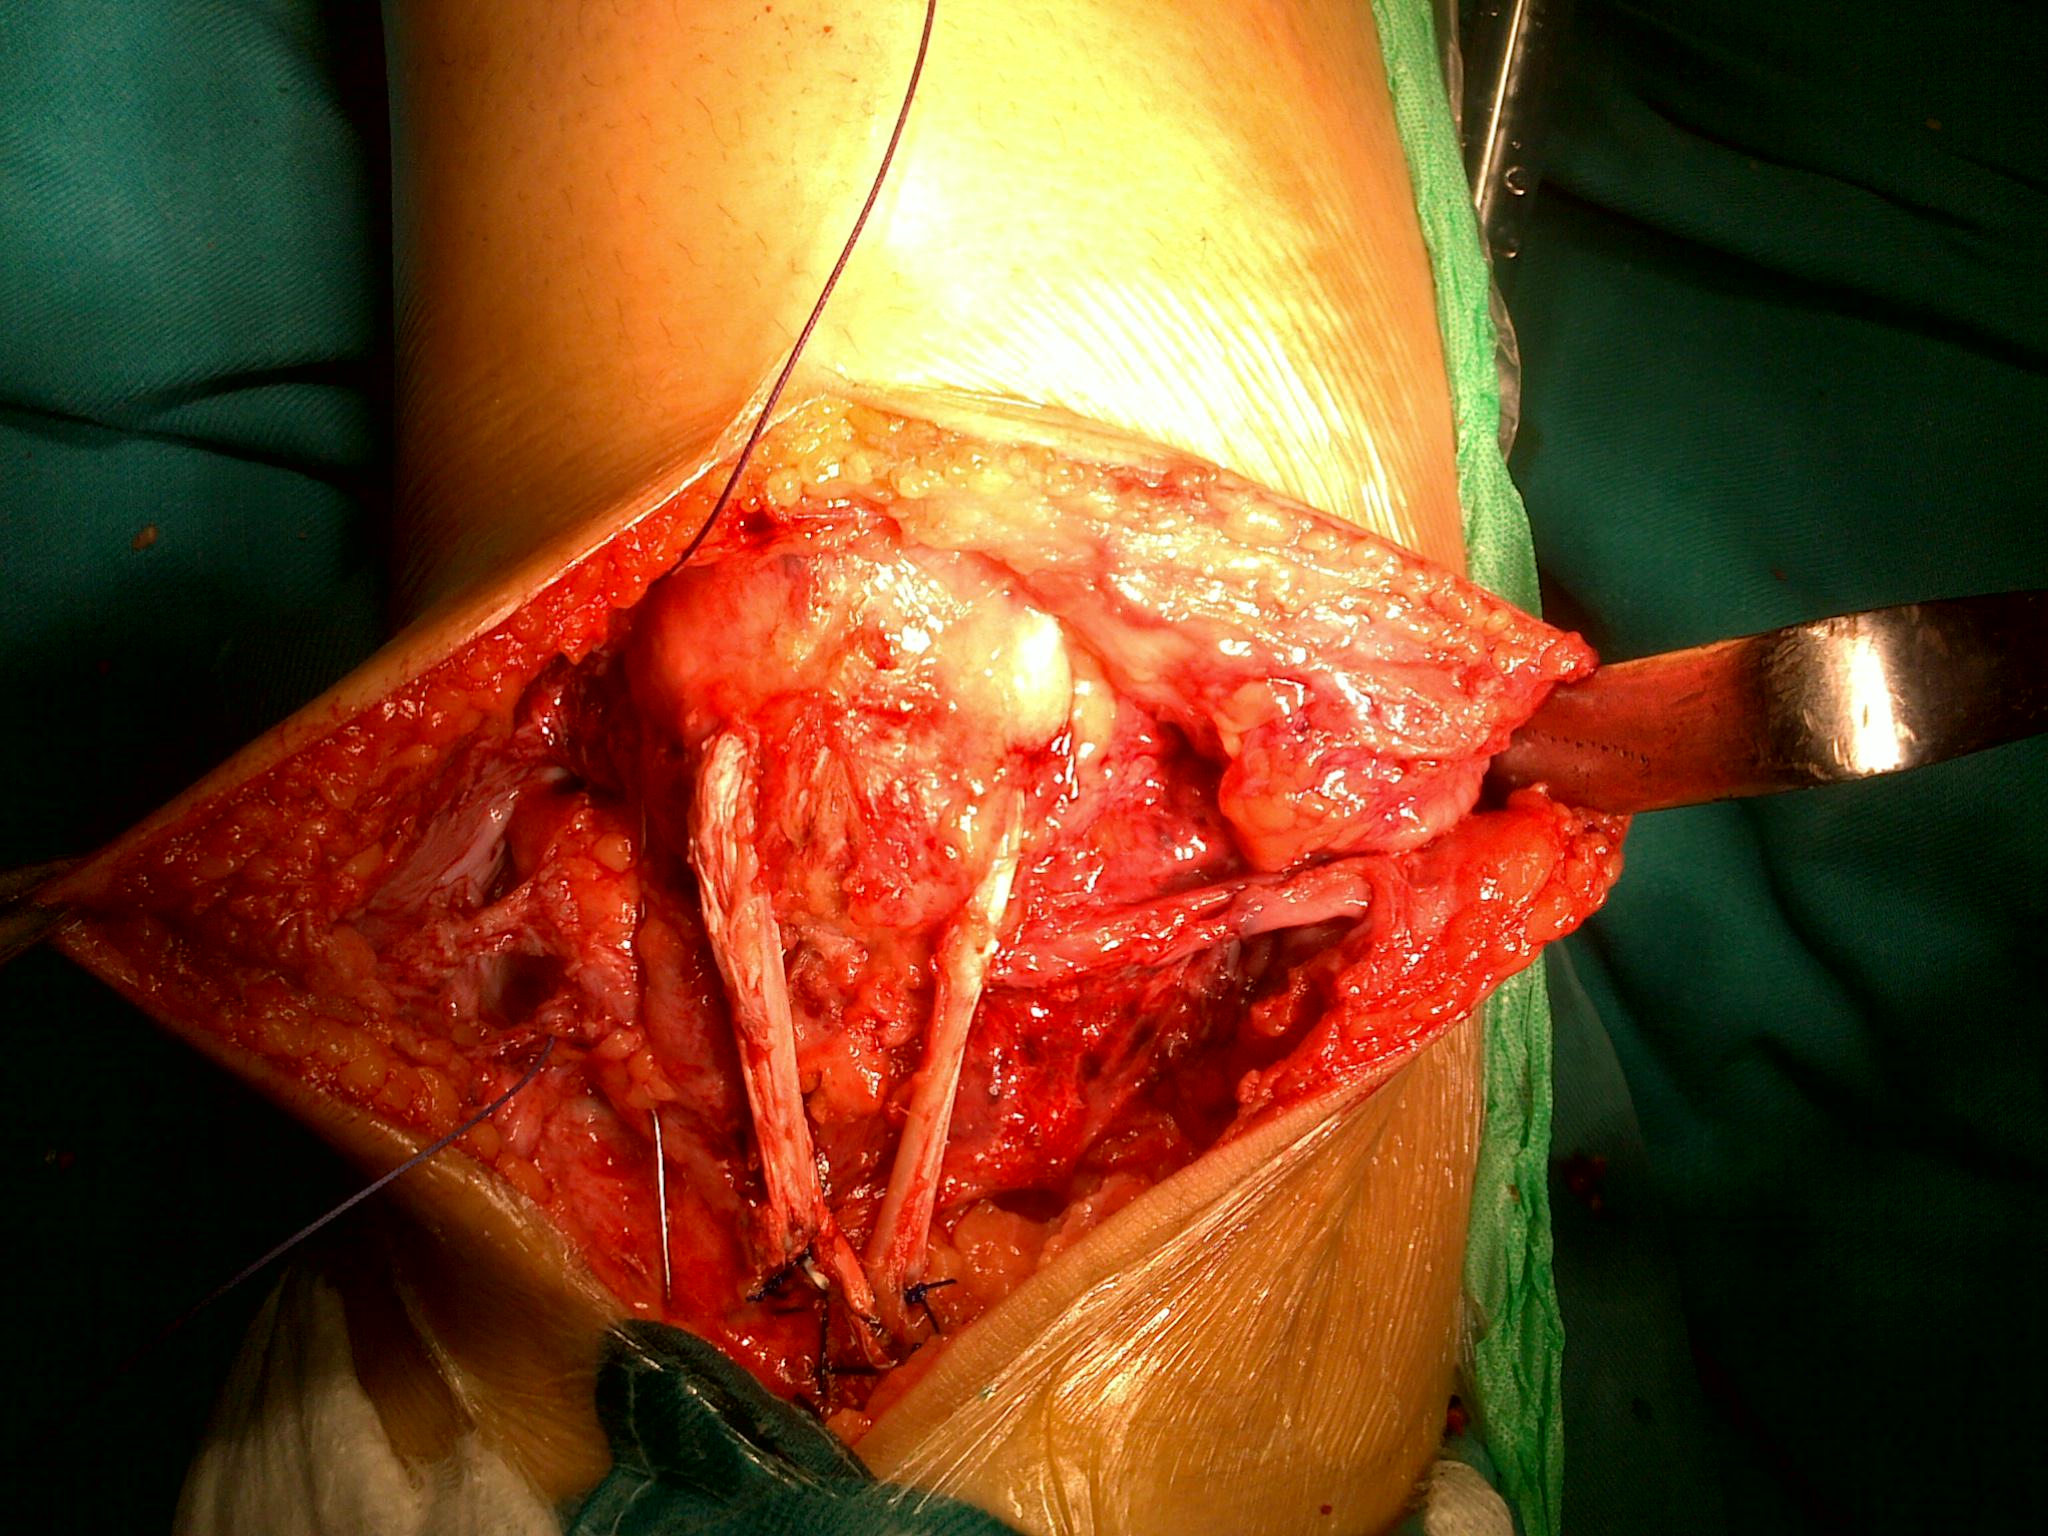

4 trường hợp bị đứt gân bánh chè đến muộn đã được tái tạo gân bánh chè bằng gân Hamstrings tự thân. Các bác sĩ tiến hành bộc lộ xương bánh chè và vùng tổn thương dưới bánh chè, làm sạch tổ chức xơ dính; sau đó lấy gân Hamstrings (có duy trì điểm bám), đo đường kính của gân và chập đôi. Tiếp đến khoan tạo đường hầm gân trong xương bánh chè (đường kính đường hầm xương phụ thuộc vào kích thước gân Hamstrings đo được); luồn gân mới qua đường hầm xương bánh chè và cố định tại vị trí bám của gân; bất động khớp gối tạm thời bằng chỉ thép. Sau phẫu thuật, bệnh nhân được bột bất động gối ở tư thế duỗi gối 3-4 tuần, sau đó sẽ được tháo bột và chỉ thép. TS. Khánh cũng nhấn mạnh, việc tập luyện, phục hồi chức năng sau mổ rất quan trọng, đóng góp 25 - 30% trong việc lấy lại chức năng gấp, duỗi gối sau phẫu thuật.

![]() Luồn gân qua đường hầm xương bánh chè và cố định. |